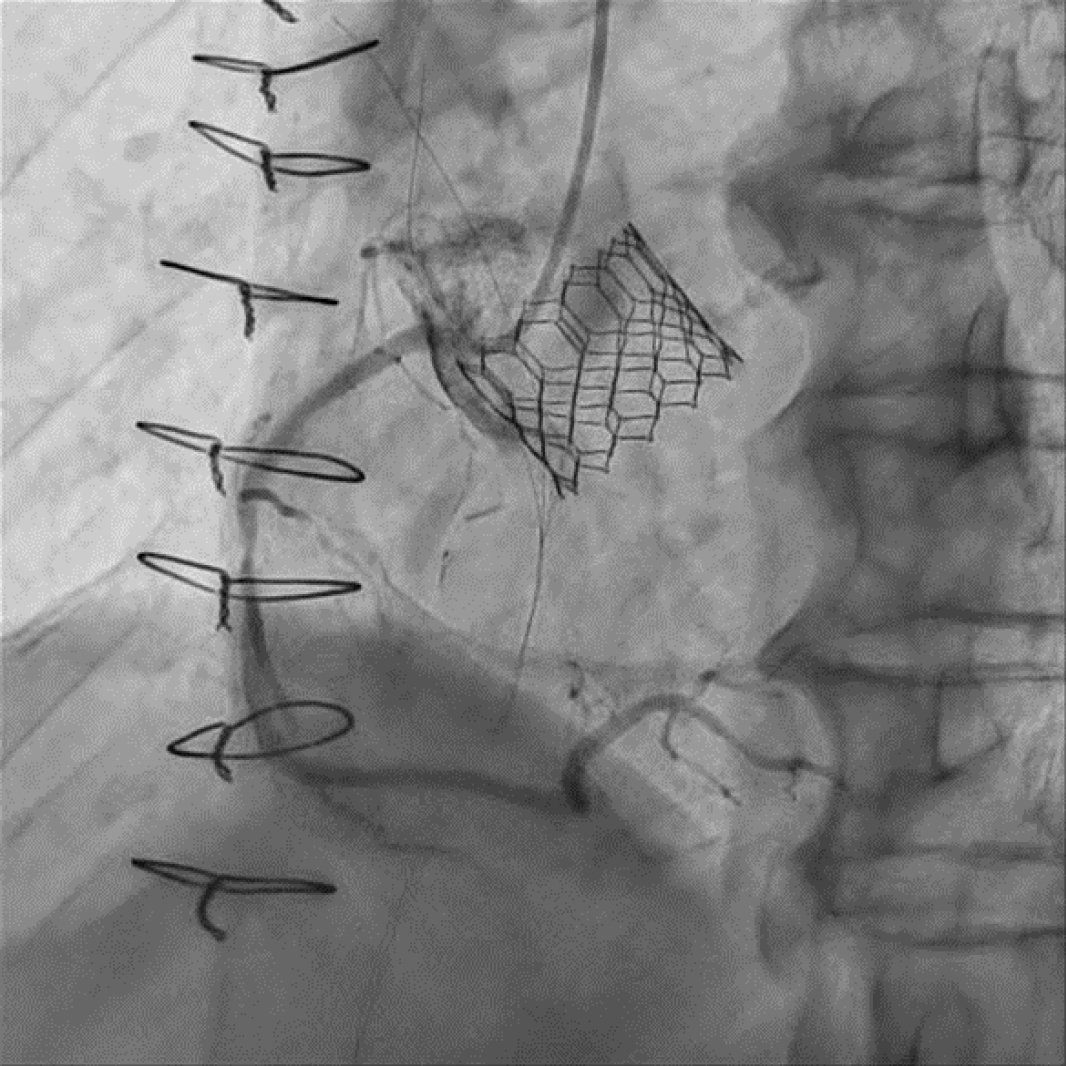

84세 남자가 아침 식사 후부터 시작된 오목 가슴 통증이 있어 응급실에 방문하였다. 과거력상 당뇨병, 고혈압이 있었고 15년전 관상동맥우회술 (coronary artery bypass graft, CABG, LIMA to LAD, Y-graft to Diagonal and Obtuse marginal branch, vein graft to PDA branch)을 시행 받았다. 또한, 1개월전 본원에서 심한 대동맥판막 협착증으로 경피적 대동맥판막 삽입술 (TAVR, Sapien 3 Ultra 26mm)을 시행 받았다. 당시 촬영한 관상동맥조영술상 LIMA graft는 잘 유지되고 있었지만 Y-graft 및 vein graft는 완전히 막혀 있는 상황이었다. 혈압 120/80 mmHg, 심박수 110회/분, 호흡수 20회/분, 체온 36.1℃, 산소포화도 98%였다. 응급실 방문 후 5분째 검사한 심전도에서 inferior leads (II, III, aVF)에 ST elevation이 있어 acute inferior ST-elevation MI로 진단하였다. 응급 관상동맥조영술상 우관상동맥 개구부 및 중위부의 심한 협착(그림 1) 이 있어 우관상동맥에 약물용출스텐트 2개를 삽입하는 일차적 관상동맥중재술(그림 2)을 시행하였다.